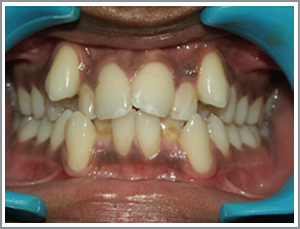

Before

After

MNL a 14 year old girl presented with the protrusion of her front teeth. (Angles class I bimaxillary proclination).

Problem list : not able to close lips due to the excessive tooth projection. Lips looking too protrusive when they were closed.

Treatment plan : extraction case – case was treated with the extraction of four first premolars. The front teeth (incisors and canines) were then taken back and the patient had a pleasing appearance and could close her lips.

Treatment time : 20 months